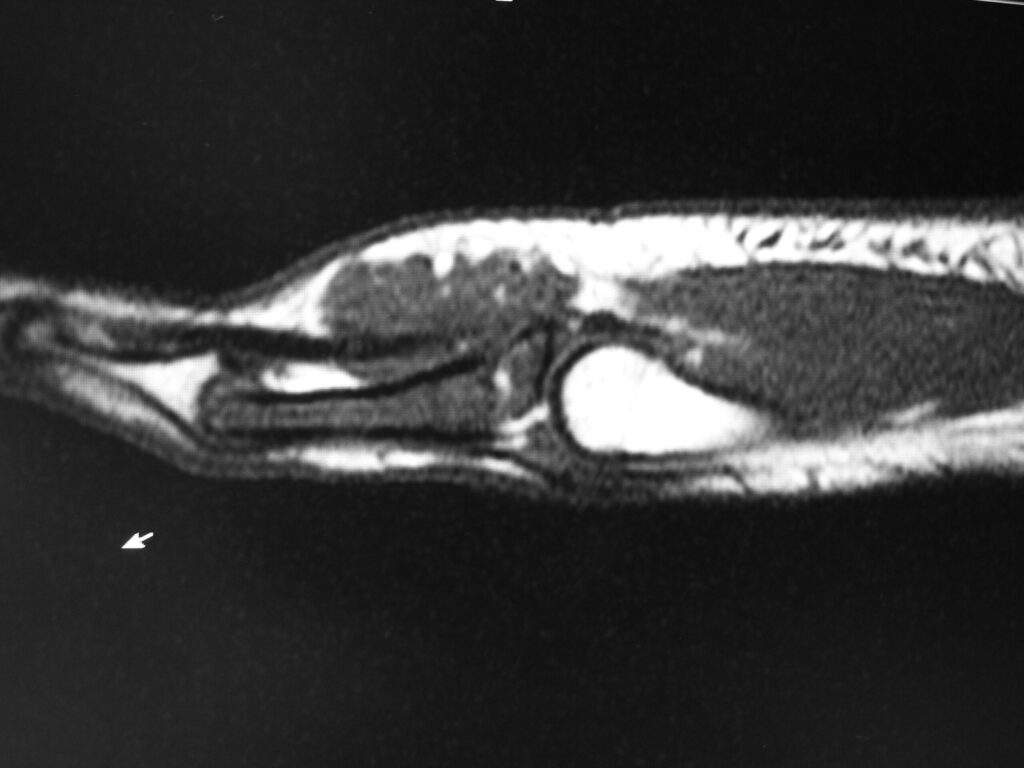

MRI

• Isointense to muscle T1

• Low to intermediate T2

• May bloom on gradient echo (hemosiderin deposition)

• May demonstrate intense enhancement

Fig. 2-5: MR images of the hand with a giant cell tumor of tendon sheath shows a mass isointense to muscle on T1W and intermediate to high signal on T2W images. The lesion does not infiltrate the bone.